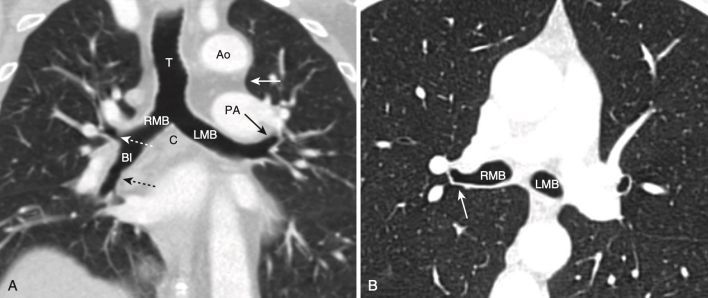

- Ở hầu hết mọi người, có một khoảng trống có thể nhìn thấy ngay dưới cung động mạch chủ nhưng ở trên động mạch phổi được gọi là cửa sổ chủ – phổi (aortopulmonary window, APW) (lưu ý không nhầm với cửa sổ chủ phế là một thuật ngữ để chỉ khiếm khuyết vách chủ – phổi bẩm sinh hiếm gặp). Cửa sổ chủ phổi là một mốc quan trọng, vì đây là vị trí phổ biến xuất hiện các hạch bạch huyết. Ở ngang mức hoặc thấp hơn một chút, khí quản chia đôi ở đường gờ giữa (carina) thành các phế quản chính bên phải và bên trái (Hình 14).

- Thấp hơn một chút là phế quản chính phải và trái và các phế quản trung gian. Phế quản chính bên phải có hình dạng một cấu trúc hình tròn, chứa khí và sẽ trở thành hình ống khi phế quản thùy trên bên phải xuất hiện. Sau phế quản trung gian không có gì ngoài mô phổi (Hình 15).

- Phế quản chính bên trái sẽ có dạng hình tròn chứa khí ở bên trái.